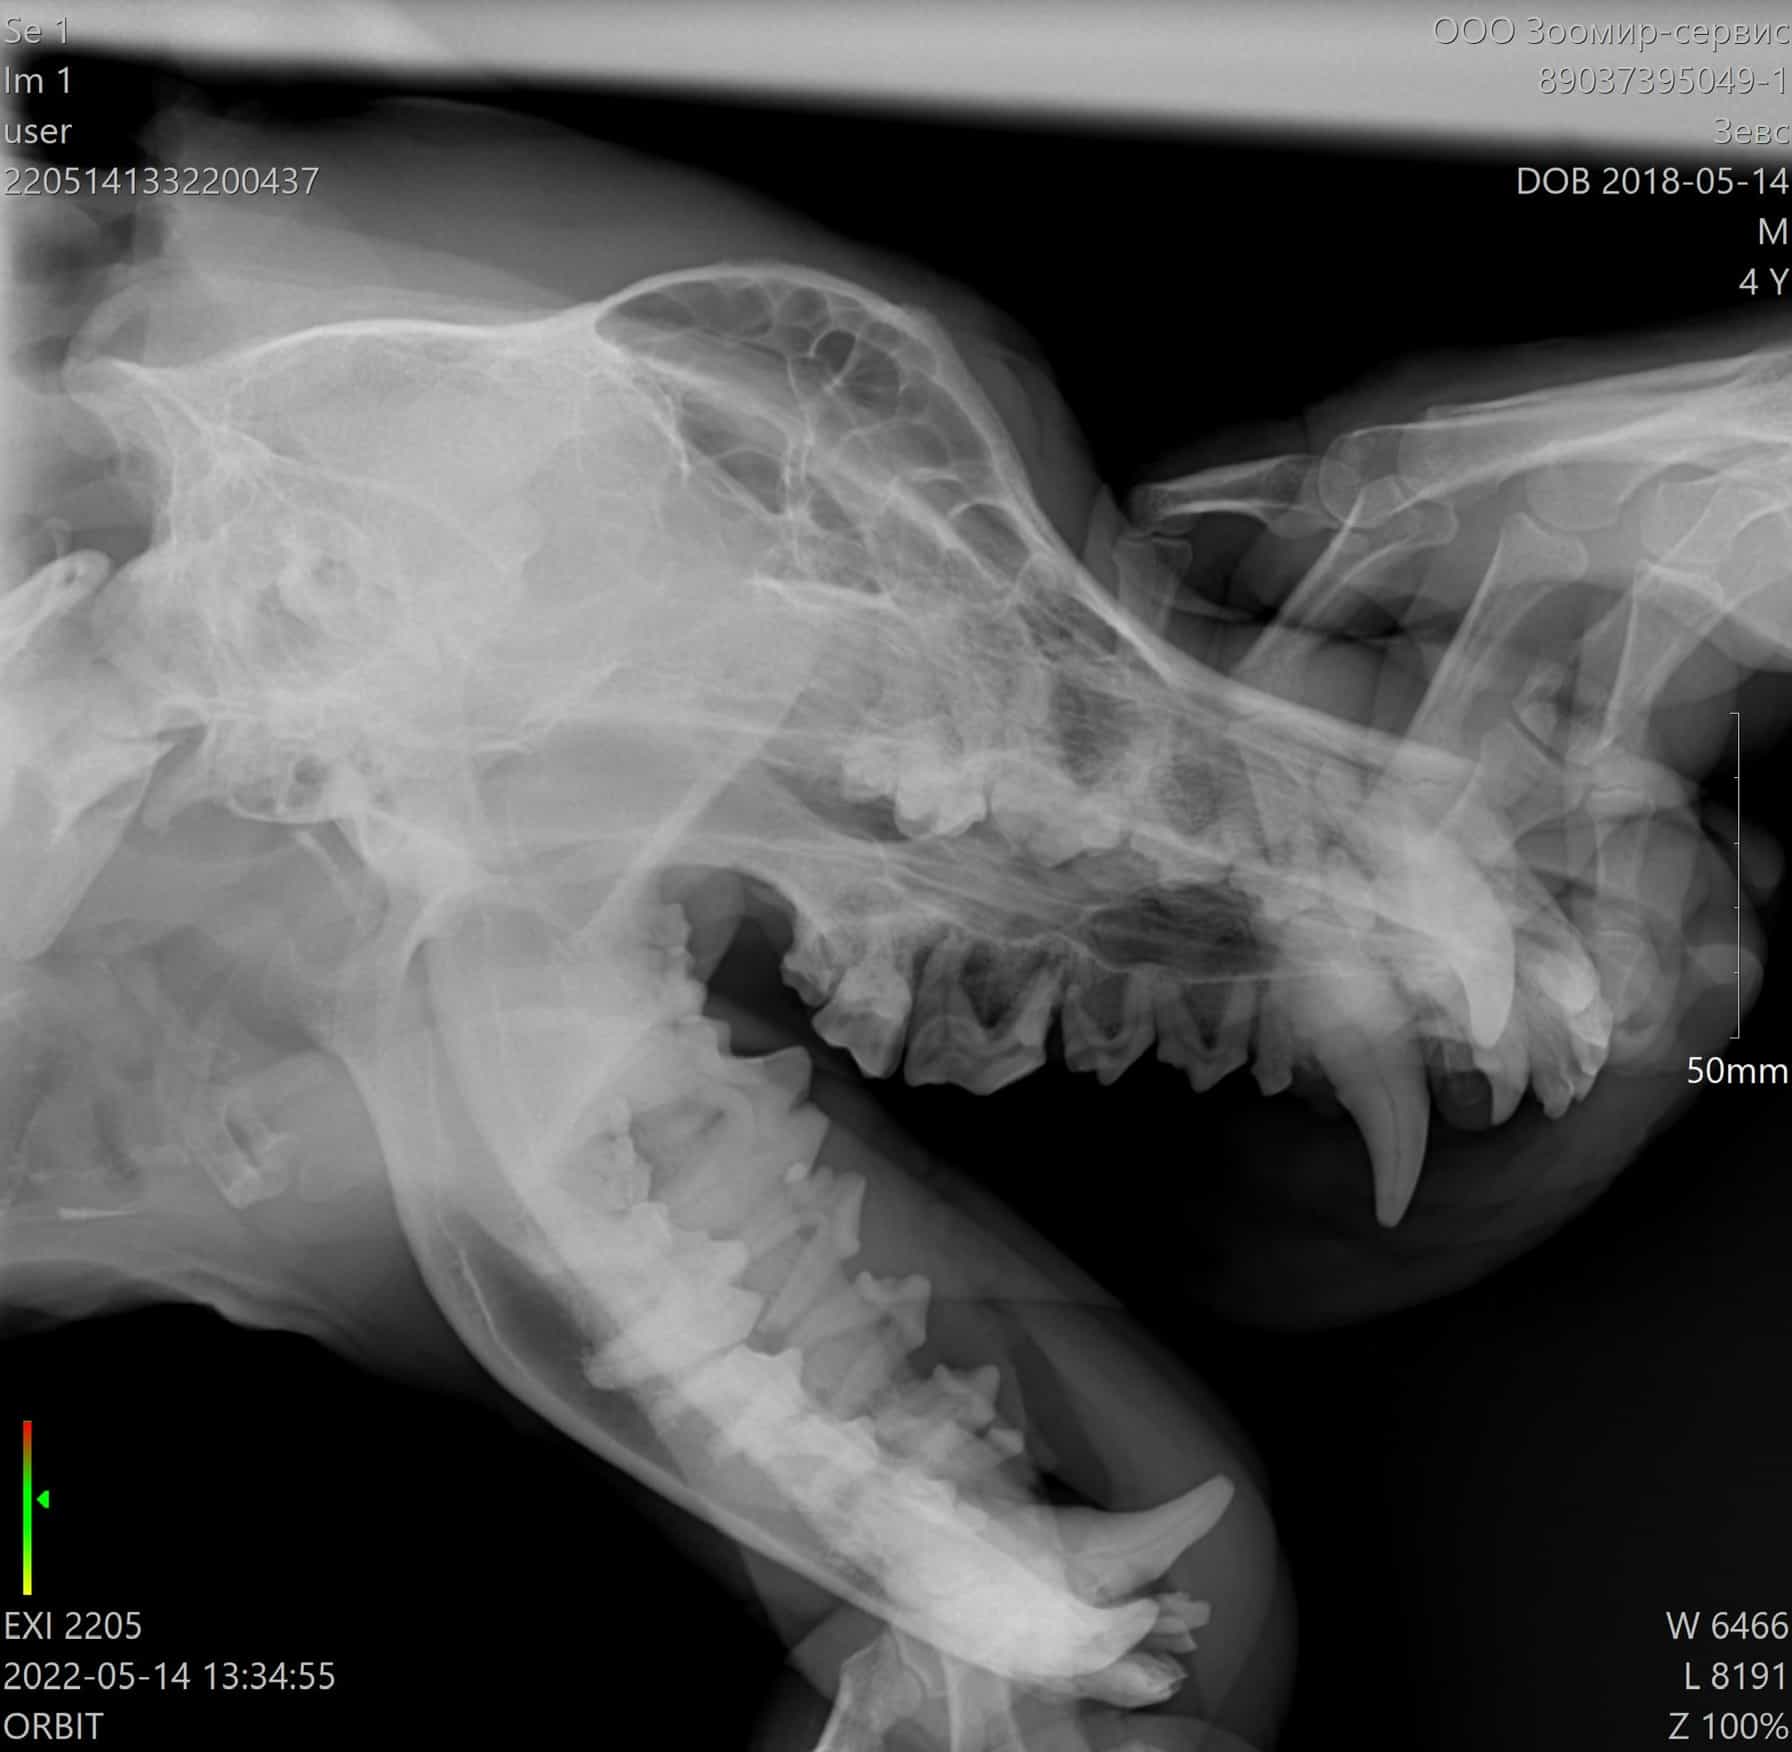

Расковыряла болячку под глазом.

Думаю мое первое ощущение правильное, это свищ.

Значит при кастрации еще и зуб удалять.

По УЗИ у нас все по возрасту. Лишнего ничего не обнаружено. Селезенка чистая, треугольная, однородная. Желчный и мочевой однородные, без взвеси и конкрементов. Печень слегка увеличена, есть небольшой акцент на стенках сосудов. Почки спокойные.

Простата сейчас несколько увеличена, есть кисты.

Так что все по плану, 14 мая кардиолог и если все ок, кастрация и скорее всего зуб, если меня не убедят в обратном.

Хочу сделать ему рентген, глянуть на глотку, пищевод и трахею и, наверное, подавать флюкостат(флюконазол). Он за последний месяц только попав под наше крыло получал антибиотики трижды: что-то у волонтеров от простаты, амоксициклин после операции и бисептол.

По моему описанию, он считает, что есть частичный паралич или срастание хрящей глотки.